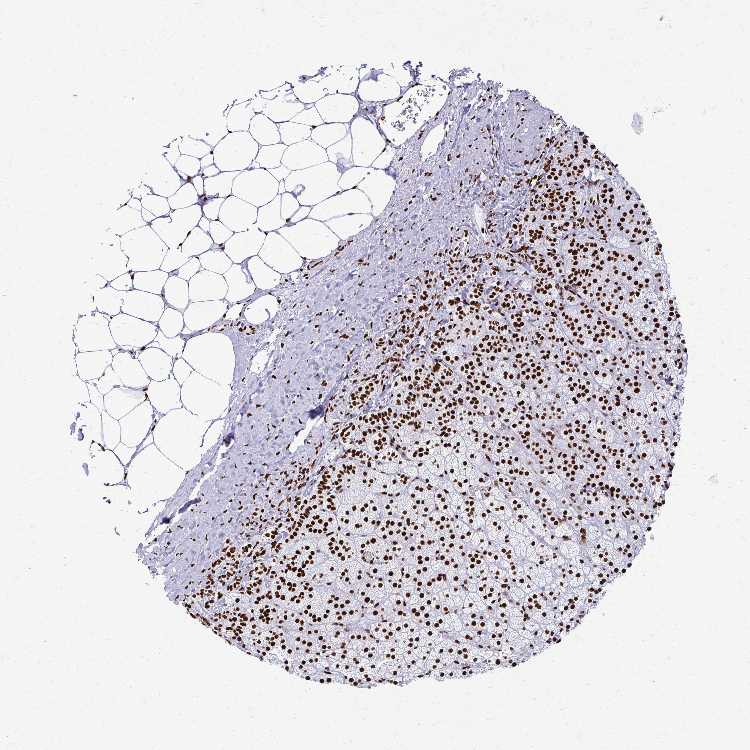

ADRENAL GLAND - Antibody stainingi

Antibody staining in the annotated cell types in the current human tissue is reported as not detected, low, medium, or high, based on conventional immunohistochemistry profiling in selected tissues. This score is based on the combination of the staining intensity and fraction of stained cells.

Each image is clickable and will lead to virtual microscopy that enables deeper exploration of all samples and also displays staining intensity scores, fraction scores and subcellular localization as well as patient and tissue information for each sample.

Antibody HPA047513Antibody HPA054689Antibody CAB009886

Glandular cells HighHighMedium